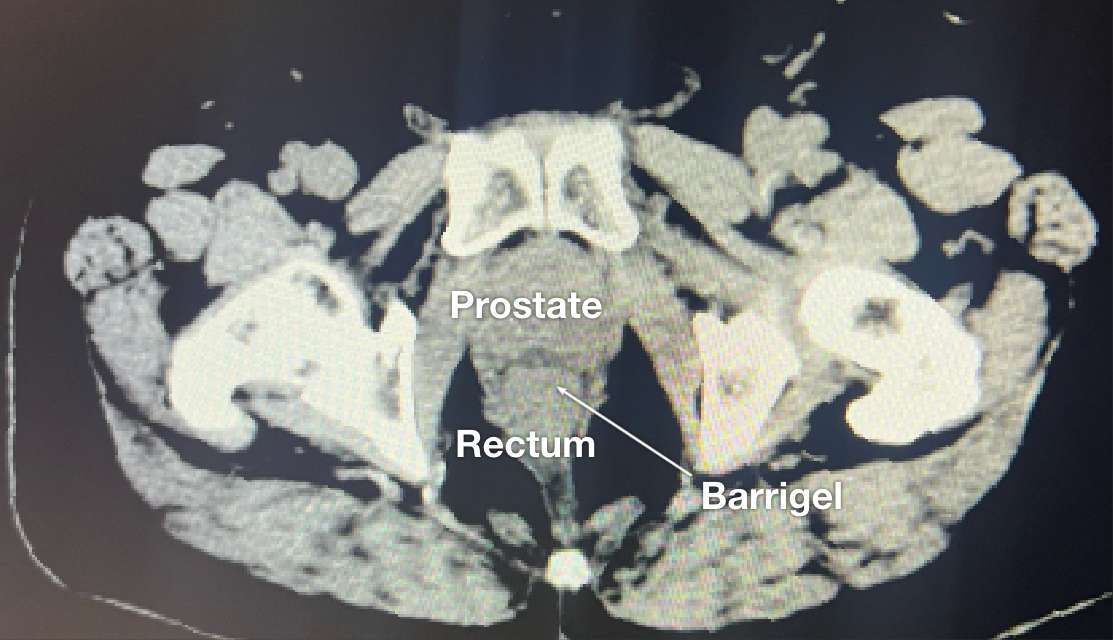

CT image courtesy of Suraj Singh, MD

Radiation Oncologist, Colorado, United States